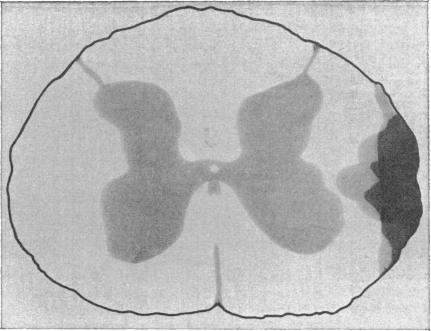

1. The lateral cervical cord of vagotomized, anaesthetized cats was superficially lesioned at the C3 or the C7 level before or after midcollicular decerebration.2. These cord lesions eliminated the inhibition of diaphragmatic discharge caused by chest compression. Previous work (Remmers, 1973) indicates that this change can be attributed to loss of reflex inhibition of inspiratory activity by intercostal afferents, probably as a result of interruption of tracts ascending in the lateral columns.3. Decerebrate cats with bilateral cervical cord lesions displayed abnormal respiratory patterns, ranging from apnoea to apneusis.4. The results are consistent with the hypothesis that the lateral columns carry proprioceptive feed-back from intercostal mechanoreceptors which promotes rhythmic breathing in the anaesthetized decerebrate cat.